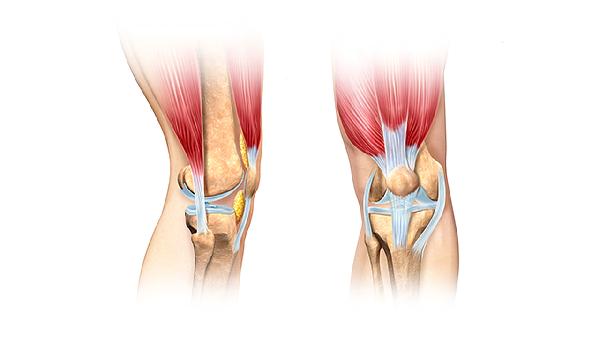

O型腿或X型腿会造成视觉身高损失,通过矫形鞋垫可改善2厘米左右步态差异。专业形体训练能纠正骨盆前倾,使实际身高得到充分展现。服装搭配选择竖条纹、同色系穿搭,避免横条纹切割身体比例。发型增加顶部蓬松度,配合修身版型服装可产生3厘米左右的视觉增高效果。

定期监测骨密度可预防骨质疏松导致的椎体压缩,40岁后每年进行双能X线吸收检测。避免吸烟和过量咖啡因摄入,这些习惯会加速骨质流失。更年期女性可考虑雌激素替代疗法维持骨量,但需评估乳腺和子宫内膜风险。日常保持正确坐姿,使用符合人体工学的桌椅,每久坐1小时起身活动5分钟。体重控制在BMI正常范围,超重会增加关节负荷加速软骨磨损。